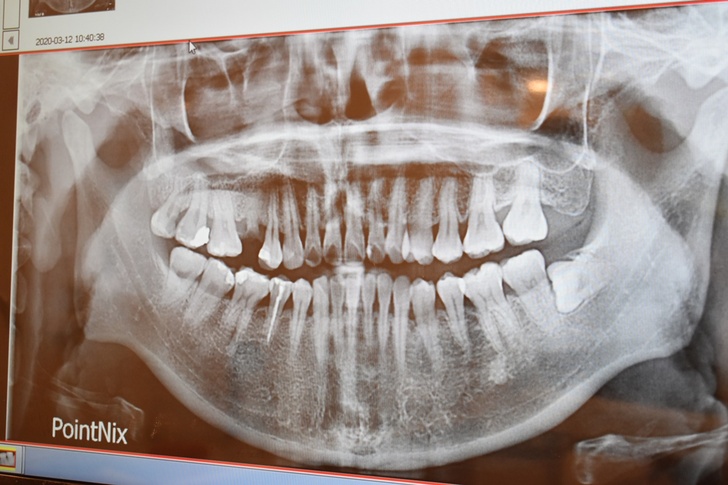

▼看診前還要先照個X光,醫師才可以確切地診斷出口腔狀況,無論是做過根管治療、缺牙、長橫只冒出一點點的智齒都可以從X光片裡看出來。

仔細看缺牙的地方,旁邊的牙齒都開始往缺口處歪了。

▼所幸都是小蛀牙補補就好,而且缺牙的部份沒有發炎的問題,骨質狀態也很不錯,經過評估是可以做一日植牙的耶!